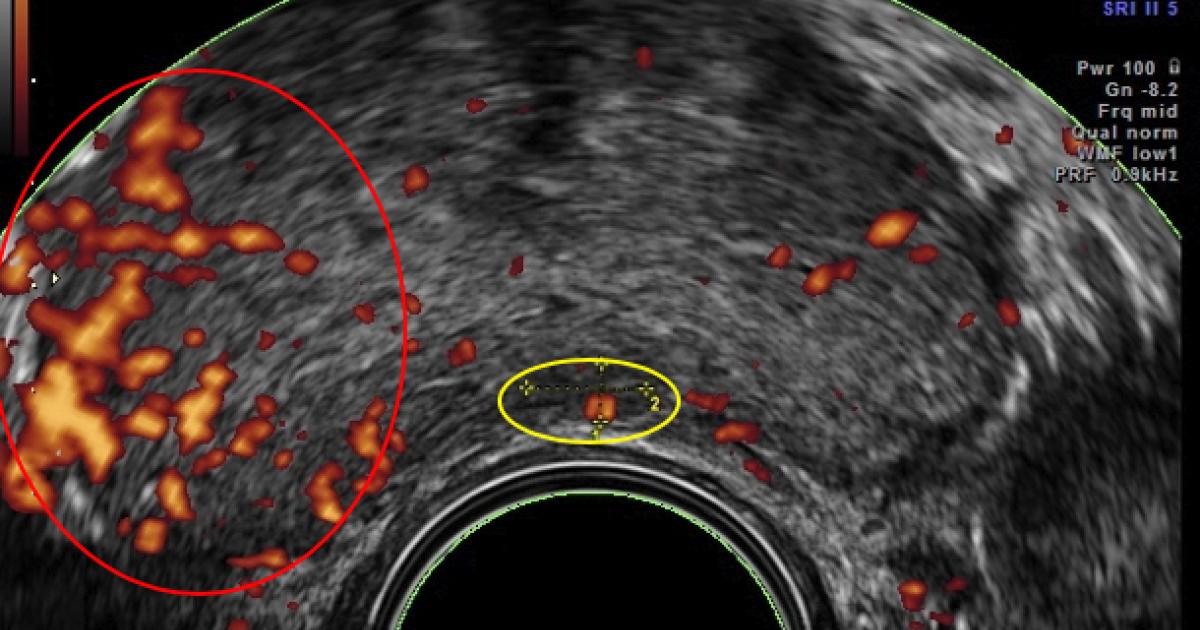

In 1994 Prof. Francois Cornud in Paris developed a better way to sample the tissue of the prostate using Doppler ultrasound. Sound waves are reflected by different tissues at different speeds, creating an image. These doppler images show tumor vascular flow the same way the Weather Doppler shows tornadoes. The presence of tumor-related blood vessels poses a hazard during the biopsy, where they can be inadvertently “nicked,” resulting in bleeding, and their presence indicates a more serious, “aggressive,” tumor. Effective cancer therapies shrink these arteries, making this 10-minute examination both safer and a means of indirectly monitoring treatment.

Since prostate cancer is, in many instances, slow-growing, early cases are often managed by watchful waiting, without invasive surgery or chemotherapy. Ultrasound imaging that detects increased tumor vascularity allows patients with biopsy-proven cancers to come in for regular scans to see if their disease is stable or if more aggressive treatment is indicated.

These technologies can focus the doppler’s sound waves on specific areas and additional data describing blood flow obtained. This data can be combined to generate a quantitative reading of the tumor vessel density to serve as a treatment guide. Vessel density of 15% is found in aggressive cancers requiring intervention, while densities of 1-2% are noted in most low-grade tumors, that can simply be monitored.